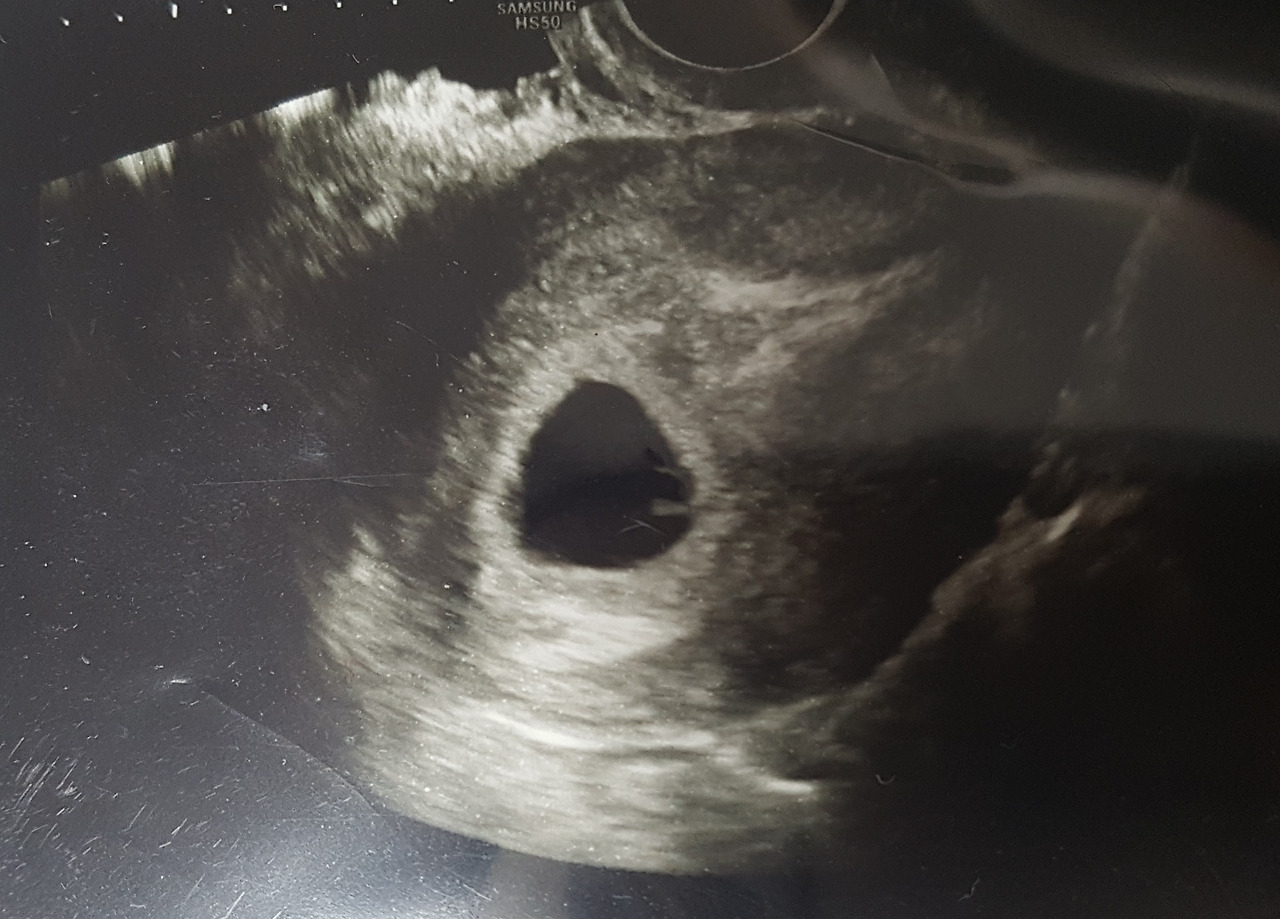

20190401_164457~01.jpg 산부인과 방문 후 확인한 초음파

의사는 초음파 속에 비치는 아기집과 난황을 보여주며 자궁에 자리를 잘 잡고 있다고 설명했다. 2주 뒤에 다시 초음파를 보고 아기 심장소리를 듣자며 그동안 안정을 취할 것을 설명한 후 진료실에서 나왔다.